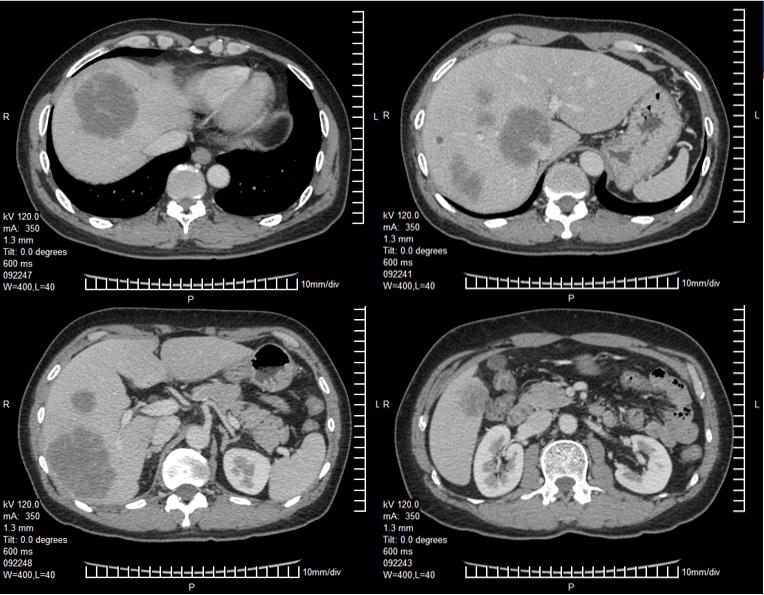

影像学检查

入院时胸、腹、盆腔等影像学检查及CT/MRI片子

3、关于转化治疗患者的评估:治疗2个周期评估属于SD还是PD?如果是SD,会不会再治疗2个周期患者会出现PR?

一般化疗最佳疗效出现在3-4个月,过早评估是否能反映真实的情况?该患者治疗2个周期后影像学评估提示肿瘤大小只有略微的改变,是否符合PD?如果是SD,会不会再治疗2个周期患者会出现PR?后续的FOLFIRI+Bev会不会是治疗时间累积足够了才体现出PR?各大指南推荐转化治疗首次评估为治疗后2个月(CSCO指南推荐每6-8周),若首次评估无疗效则建议更换方案。

患者男性,56岁,确诊右半结肠癌伴肝脏多发转移,确诊时临床危险评分(CRS)4分(具有同时性肝转移、多个转移灶、最大病灶长径>5cm、CEA>200ng/ml)属于高危患者[1]。按照ESMO推荐的对于结肠癌肝转移患者的评估标准该患者属于技术上难切除,预后差的患者,应该选取最佳全身治疗进行转化治疗[2, 3]。患者并未出现梗阻、明显出血、穿孔或其他原发肿瘤引起的症状,因此按照NCCN指南推荐全身治疗而不建议初始切除原发灶[4]。患者年轻、一般情况可,原发灶位于右半结肠,且其KRAS基因为突变型,因此推荐选择三药联合化疗(FOLFOXIRI),如患者经济上可以承受也可考虑三药或双药(FOLFOX或FOLFIRI)联合贝伐单抗[5, 6]。关于右半结肠癌的一线治疗推荐,2017版NCCN指南明确指出不考虑使用EGFR抗体;而ESMO指南对于RAS野生型、Braf野生型患者,当以肿瘤减灭为目的时首选两药联合+EGFR抗体,次选三药联合或不联合贝伐单抗。针对一线化疗对比化疗联合西妥昔单抗的左右半分析,共有两项Ⅲ期临床研究的回顾性分析结果和一项中山大学肿瘤防治中心的回顾性研究结果,在CRYSTAL、TAILOR和我们的研究中都显示化疗联合西妥昔单抗对比单纯化疗有效率、PFS和OS均未呈现显著提高[7, 8]。另外两项头对头比较双药联合贝伐单抗或西妥昔单抗的临床研究FIRE3和80405都显示两者在有效率方面无显著的差别[9]。因此如果该患者为RAS野生型仍不建议首选EGFR抗体治疗。

2程化疗后展示的患者肝脏CT无明显改变,评价为PD的原因不明。若患者因肝脏或其他部位出现新发病灶出现了病情进展,可考虑二线采用FOLFIRI联合贝伐单抗,4程化疗后肝脏病灶明显减少、缩小,评价为PR。因贝伐单抗使用后需暂停6周以上才能进行手术,因治疗间隔太长,建议该患者在停用贝伐单抗期间进行FOLFIRI方案化疗2至3疗程。手术切除原发灶和肝转移灶,病理已确认。其后患者进行了术后辅助化疗4程,患者术前行化疗4程,仅出现Ⅱ度骨髓抑制,根据NCCN指南术后可建议其行8程FOLFIRI方案或2-3程FOLFIRI方案加6-5程FOLFIRI联合贝伐单抗方案化疗,达到共6个月的围手术期化疗。

此病例患者首先因为发现肝占位入院,完善检查,诊断升结肠癌 肝转移,原发证升结肠肿瘤可手术切除,但肝内病灶多发(6个),尤其侵犯门静脉主干分叉处,该病例不能归于寡转移疾病。经过MDT会诊,转移灶初治时不可切除,暂无R0手术切除可能,鉴于原发升结肠病灶没有梗阻、出血等症状,一致建议选择转化化疗,降期争取手术治疗是其目的。依据ESMO分组意见,该病例属于组1患者。尽管是一线转化化疗效果欠佳,但是bevacizumab联合FOLFIRI的化疗获得了明显的PR效果,转化为可切除。这个病例显示出如果治疗目标是从不可切除转化为可切除,bevacizumab联合化疗还是有较好的肿瘤退缩效果。该患者总体生存达2年以上,整体治疗是成功的,MDT讨论决策至关重要。但术前评估、手术时机的选择、以及靶向用药等也存在一些需要进一步讨论的问题。

患者肝内发现6个病灶,位于右肝,有一个大肿瘤临近门静脉主干,K-RAS为突变型,术前的转化化疗有一个PR的良好反应,所以这个患者的治疗目标还是应该是治愈。所以,治疗选择一定是根治性的治疗。由于肿瘤靠近门静脉主干,手术中外科医生做了最大努力使得病灶达到肉眼R0切除,实属不易。但术后半年不到时间出现复发,是否与未采用磁共振评估肝转移灶有关,值得商榷。最近韩国有一项多中心回顾研究提示对于临床完全缓解的肠癌肝转移患者,普美显-磁共振漏诊率明显低于增强CT(22.0% vs. 64.8%)。因此,还是要强调肝脏转移瘤常规行磁共振检查。